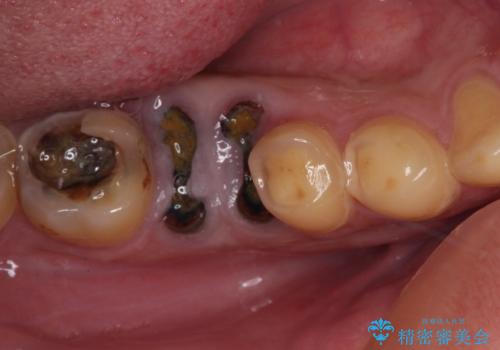

部分矯正を併用した奥歯のインプラント治療